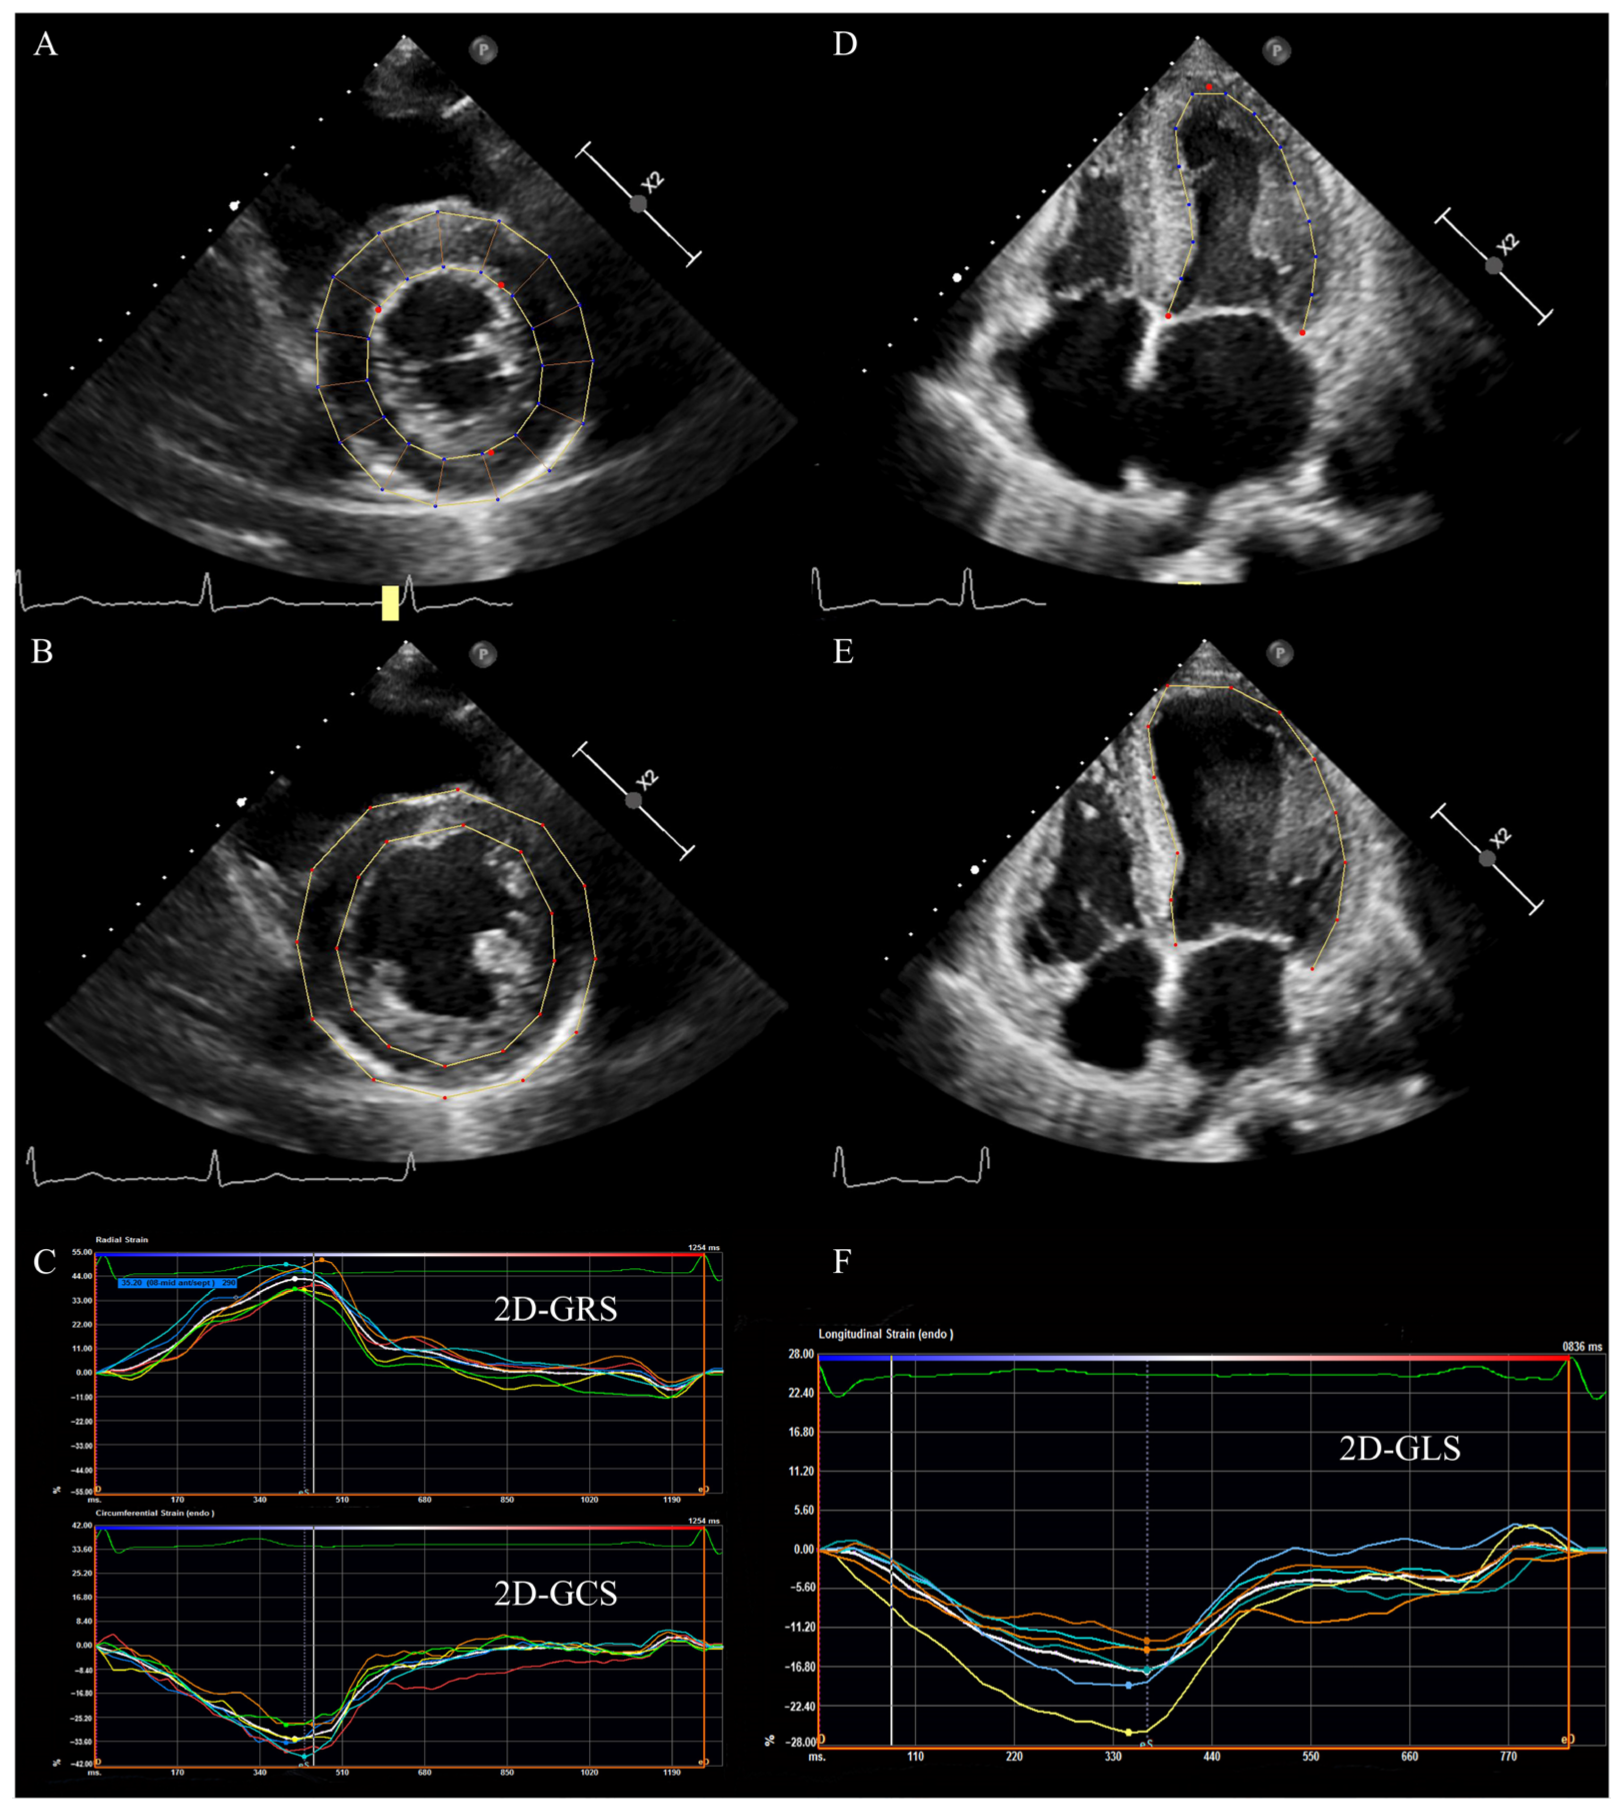

2.1. Two-Dimensional Speckle-Tracking Echocardiography